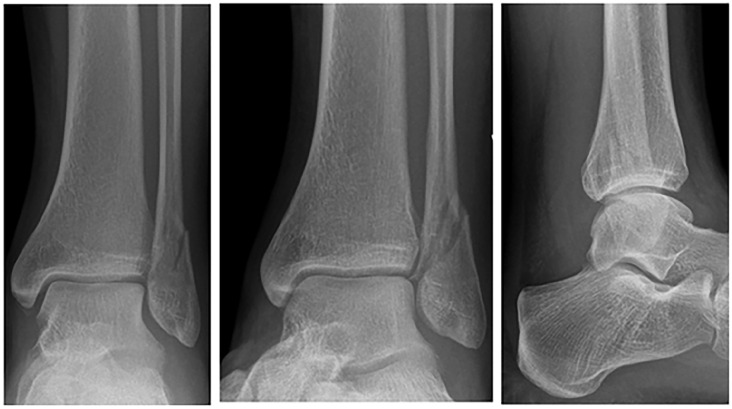

背景:踝关节骨折是一种常见的骨科损伤,其治疗主要取决于骨折的稳定性。Lauge-Hansen分类系统根据损伤机制和累及的韧带对骨折进行分类。旋后外旋(SER) 2型骨折对应于稳定的韦伯B型骨折,传统上采用非手术治疗,而SER 3和SER 4型骨折以联合破坏为特征,通常需要手术干预。我们假设一些表面稳定的损伤可能涉及额外的结构,挑战传统的治疗方法。本研究旨在确定影像学上稳定的SER 2骨折中SER 3和SER 4踝关节损伤的发生率。方法:该研究使用了黄金海岸医院和卫生服务(GCHHS)纵向队列的基线数据。在GCHHS骨折诊所就诊且SER 2骨折影像学稳定的患者被邀请参与研究。符合资格标准的患者接受踝关节磁共振成像(MRI)来评估关节联合韧带和踝关节韧带的完整性。结果:共招募56名参与者,女性38人(68%),男性18人(32%),平均年龄47.2岁。所有患者在x线评估中均有稳定的关节联合,并被诊断为稳定的SER 2踝关节骨折。MRI扫描显示,71% (n = 40)的SER 2损伤符合标准,25% (n = 14)的SER 3损伤伴胫腓后下韧带(PITFL)完全破裂,4% (n = 2)的SER 4损伤伴胫腓后下韧带(DL)破裂。这些结果挑战了影像学上稳定的SER - 2骨折在所涉及的其他结构方面始终稳定的假设。结论:该研究强调了相当一部分看似稳定的踝关节骨折涉及的结构比以前认为的更多。这表明SER 3和SER 4损伤的处理可以包括非手术治疗。证据等级:III级,队列研究。

Background: Ankle fractures are common orthopaedic injuries, and their management is primarily determined by fracture stability. The Lauge-Hansen classification system categorizes fractures according to mechanism of injury and ligaments involved. Supination external rotation (SER) type 2 fractures correspond to stable weber B fractures and are traditionally treated nonoperatively, whereas SER 3 and SER 4 fractures, characterized by syndesmosis disruption, typically require surgical intervention. We hypothesize that some apparently stable injuries may involve additional structures, challenging the conventional treatment approach. This study aims to determine the prevalence of SER 3 and SER 4 ankle injuries among radiographically stable SER 2 fractures.

Method: The study used baseline data from a longitudinal cohort conducted at Gold Coast Hospital and Health Service (GCHHS). Patients attending the GCHHS fracture clinic with radiographically stable SER 2 fractures were invited to participate. Those meeting the eligibility criteria underwent ankle magnetic resonance imaging (MRI) to evaluate the integrity of syndesmotic and ankle ligaments.

Results: Fifty-six participants were recruited, 38 (68%) female and 18 (32%) male, with a mean age of 47.2 years. All had stable syndesmoses on radiographic assessment and diagnosed with stable SER 2 ankle fractures. MRI scans revealed that 71% (n = 40) met the criteria for SER 2 injuries, 25% (n = 14) for SER 3 injuries with complete ruptures of posterior inferior tibiofibular ligament (PITFL), and 4% (n = 2) for SER 4 injuries with PITFL and deltoid ligament (DL) ruptures. These results challenge the assumption that radiographically stable SER 2 fractures are consistently stable in terms of additional structures involved.

Conclusion: The study highlights that a considerable proportion of seemingly stable ankle fractures involve more structures than previously thought. This suggests the management of SER 3 and SER 4 injuries could include nonoperative treatment.